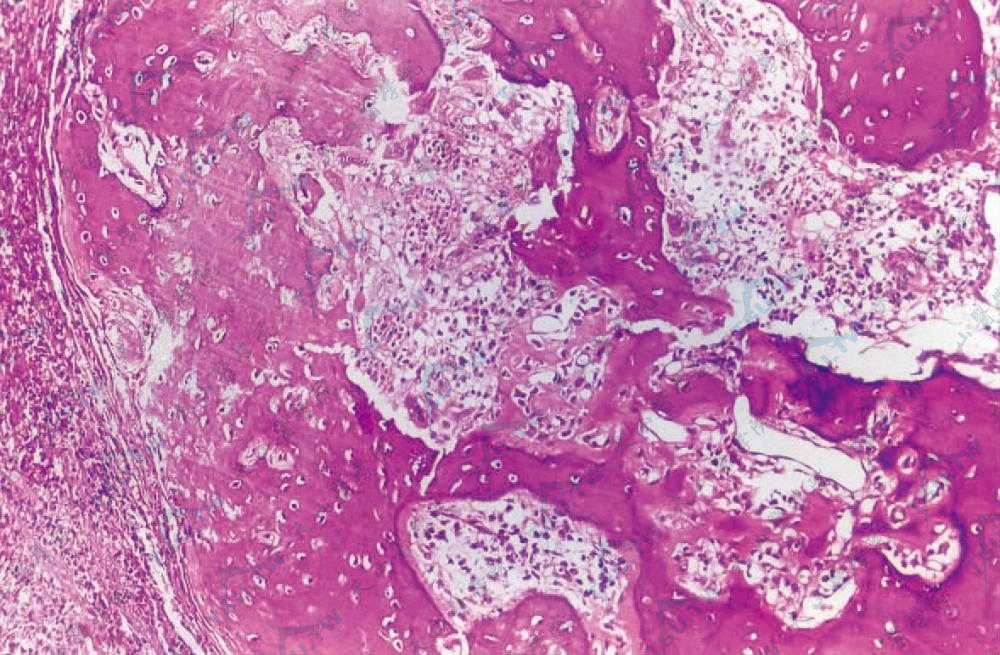

化生性骨化:真皮内见成骨细胞和破骨细胞,骨组织周围有明显的血管和细胞的组织反应,见大量炎细胞浸润